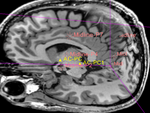

this is the target orientation in which is AC-PC line is horizontal and the inter-hemispheral midline is vertical lleft this is the MRI image in the original position.

moving image

MRI